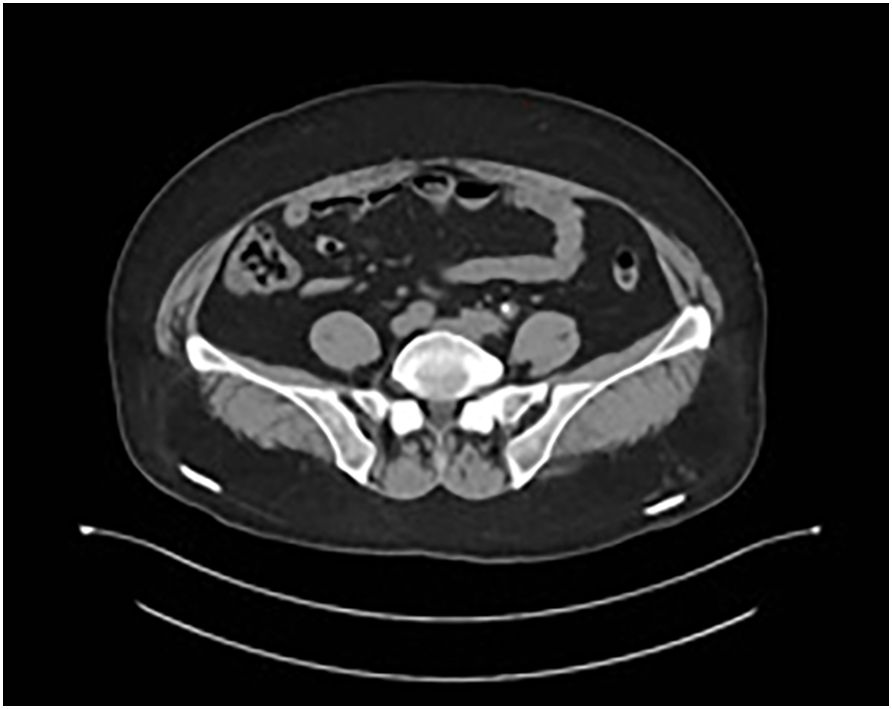

Immunohistochemical staining confirmed the diagnosis of SCNEC: synaptophysin (diffuse+), CD56 (membranous+), chromogranin A (focal+), and a Ki67 proliferation index exceeding 75%. PD-L1 expression, assessed using the 22C3 pharmDx assay, was low (combined positive score [CPS] = 2) (Figure 3). Staging investigations excluded metastatic disease outside the regional lymph nodes.

Figure 3

Histological image showing densely packed cells with dark nuclei and interspersed brown-stained regions indicating protein expression or tissue structures. The background is light with a mix of closely grouped cells.

Figure 3. PD-L1 immunohistochemical staining using the EnVision method (×200), showing low expression (CPS = 2).